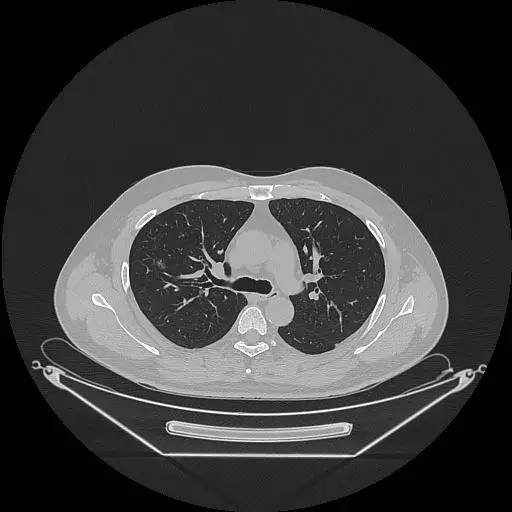

男,47岁,查体发现右肺小结节8月余。

[影像描述]

右肺上叶可见直径约7mm磨玻璃样结节,其内见空泡影,有浅分叶及血管集束征象,增强扫描无强化,余肺、纵隔未见明显异常。

右肺上叶不典型腺瘤样增生(AAH)

AAH的影像学特点为呈类圆形小病灶,边界清楚,淡至中等密度均匀的毛玻璃或磨砂玻璃阴影,不遮蔽其下的肺实质,多数在5 mm以下。